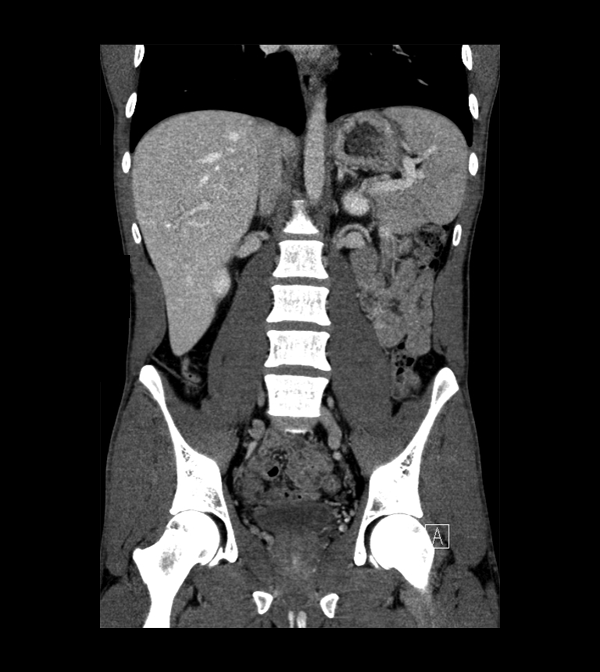

Body

Covers abdominal CT anatomy.